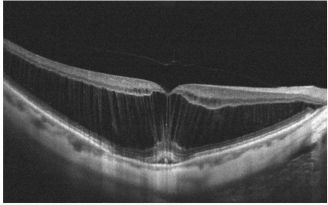

Foveoschisis:[19]

This is characterized by intraretinal splitting at the fovea with vertical tissue bridges connecting the inner and outer retina. Fluorescein angiography does not show petaloid macular leak as is seen in CME. Visual acuity may be disproportionately good despite the increase in the central macular thickness.